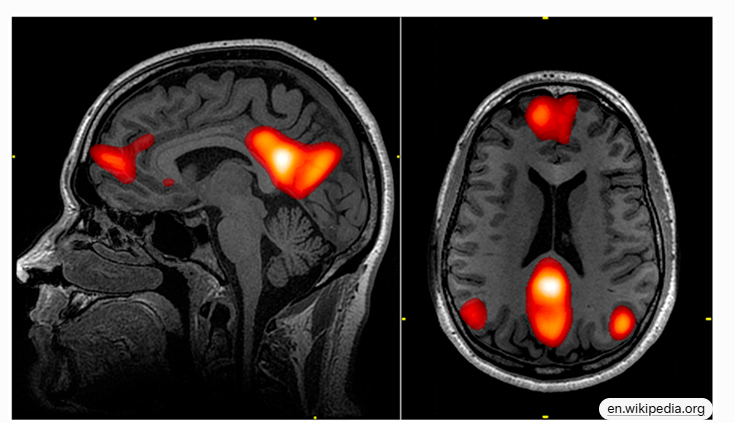

DMN是指大脑中一组相互连接的区域,这些区域在个体不专注于外部任务时(如休息、日梦或内省时)表现出高度活跃。它也被称为“默认网络”或“内侧额顶叶网络”(medial frontoparietal network, M-FPN)。DMN的核心在于它支持内部导向的认知过程,而不是外部刺激驱动的任务。

DMN主要包括以下核心区域,这些区域通过白质束(如胼胝体和扣带束)高度连接,形成一个功能集线器:

- 后扣带皮层(PCC)和楔前叶(Precuneus):整合注意、记忆和感知;PCC的腹侧部分处理自我相关任务,背侧部分涉及意识。

- 内侧前额叶皮层(mPFC):负责自我加工、自传记忆和决策。

- 角回(Angular Gyrus):连接感知、注意、空间认知和情节记忆。

- 子系统:包括背内侧子系统(思考他人)和内侧颞叶子系统(自传记忆和未来模拟)。

DMN的结构和功能连通性高度重叠,使用fMRI的种子分析或任务失活方法定义。人类DMN比灵长类更发达,尤其是mPFC区域。 以下是DMN的典型脑区示意图,用于可视化其分布: